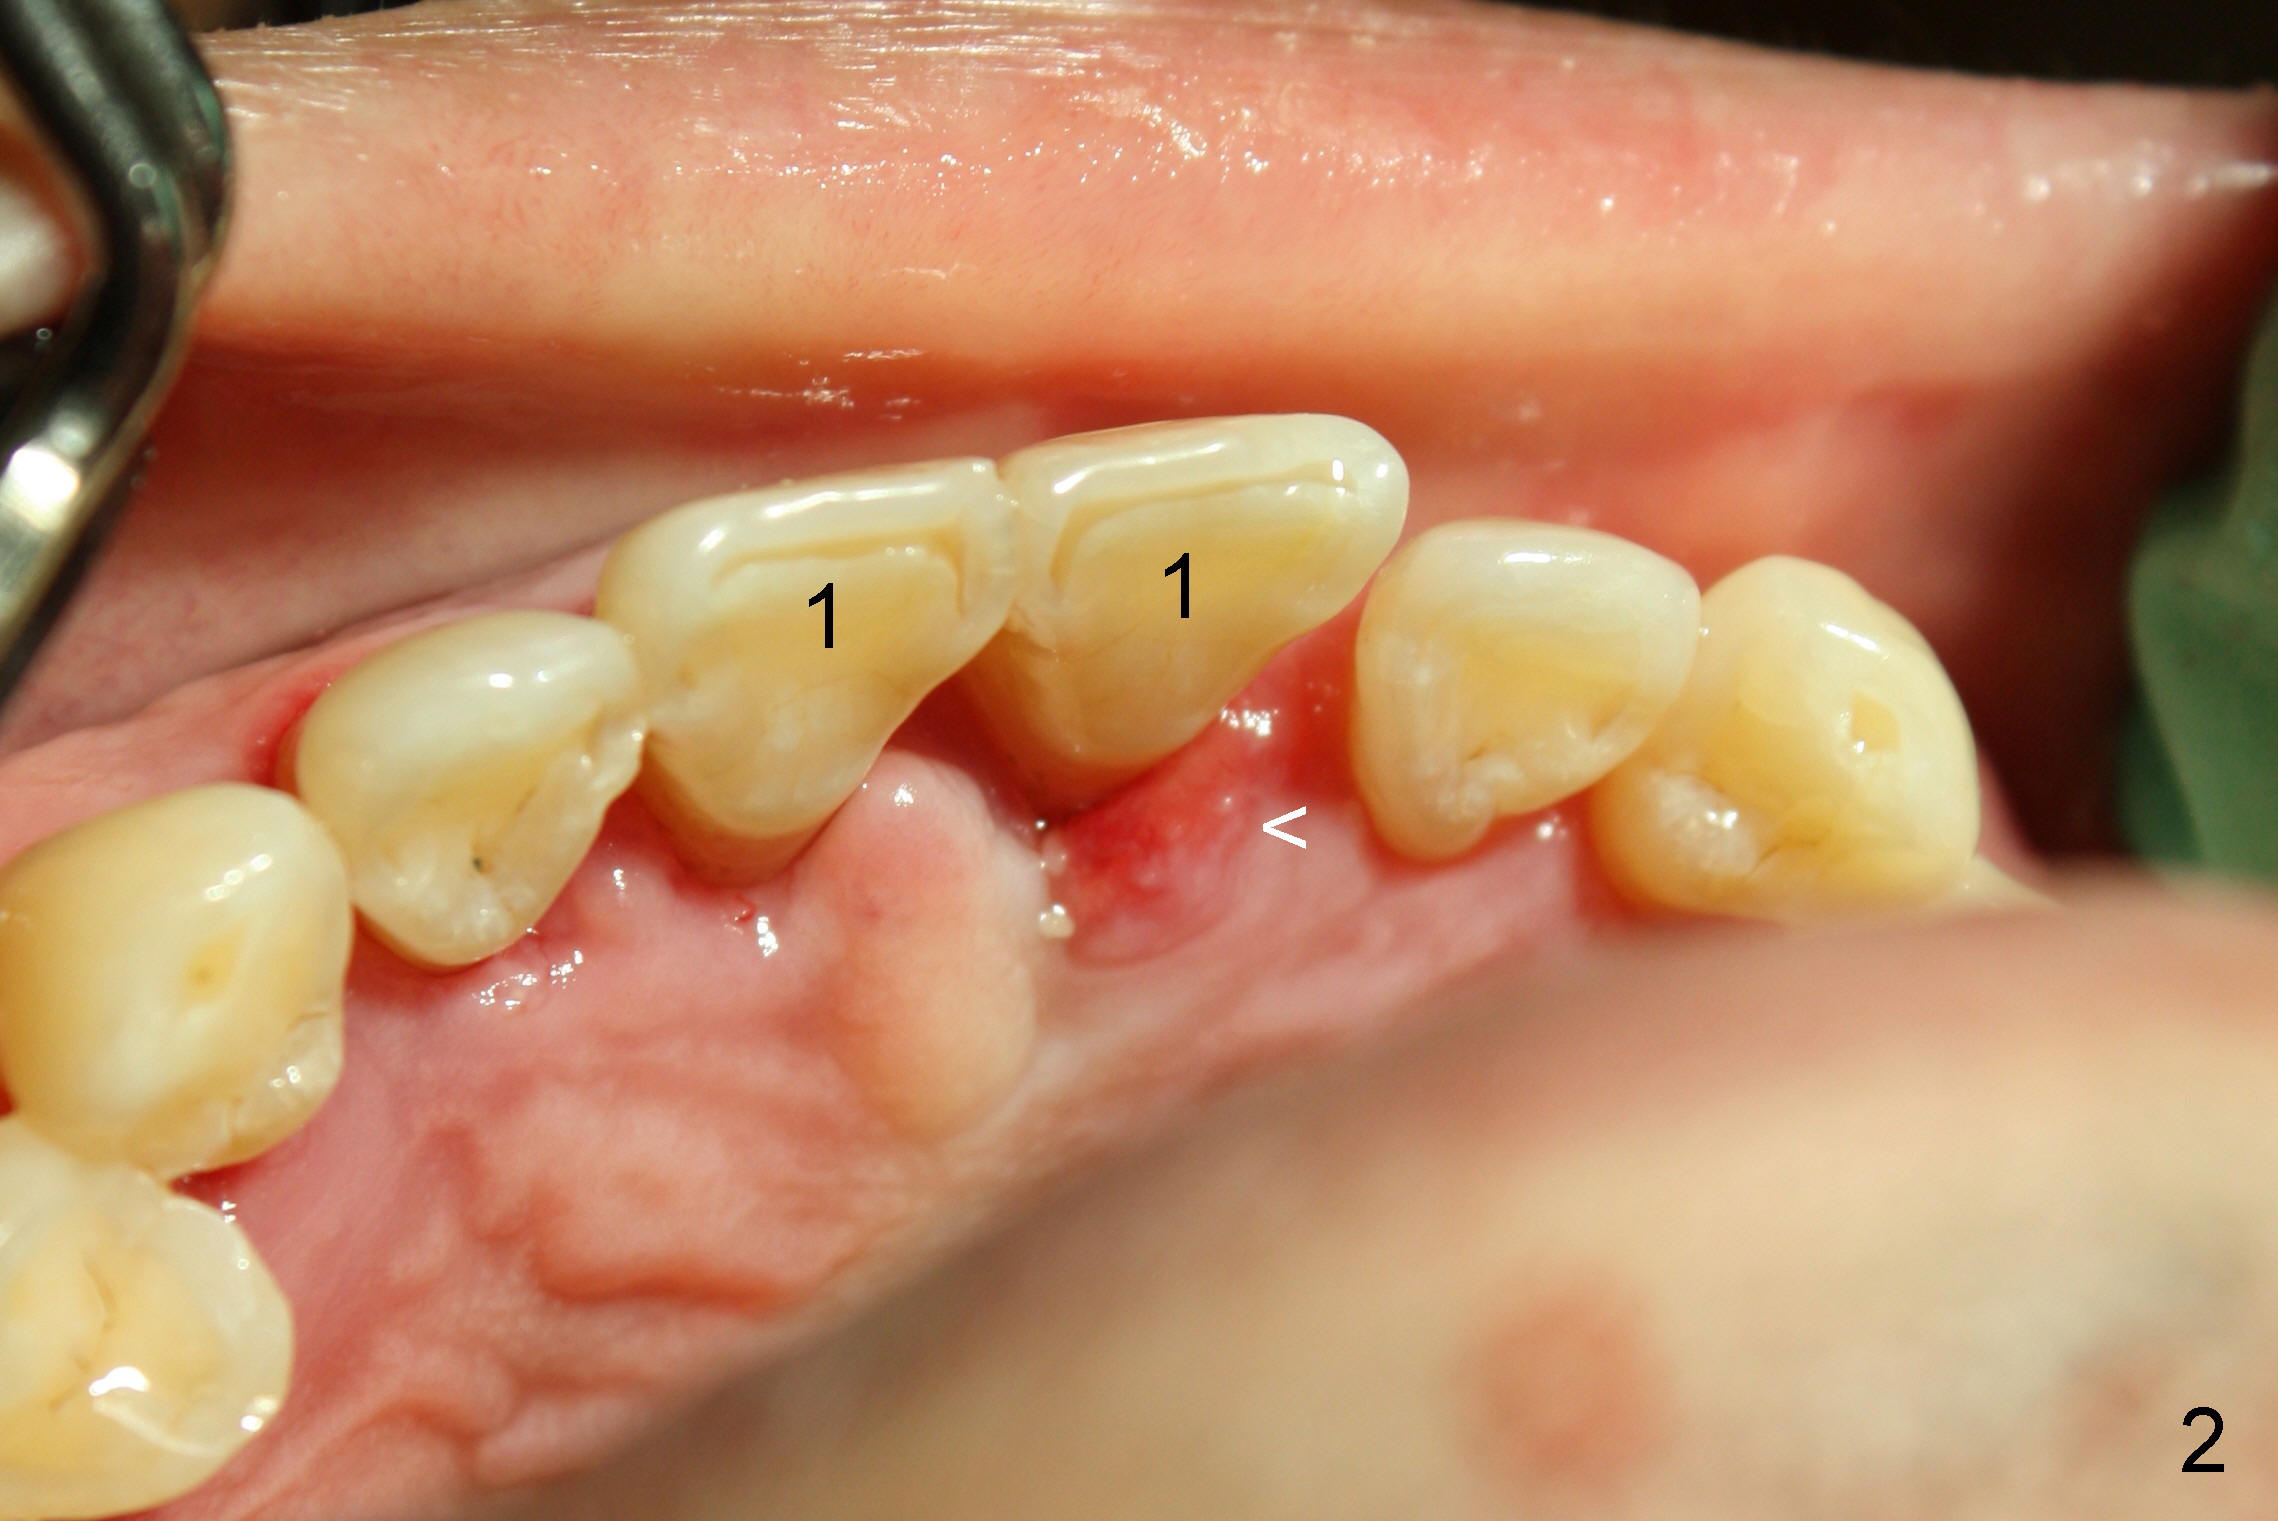

A 44-year-old man has advanced periodontitis (Fig.1,2). The infection resolves substantially 5 days post scaling & root planing (Fig.4,5). The two centrals have severe bone loss (Fig.3) and are going to be replaced by 5x20 mm implants (Fig.6).